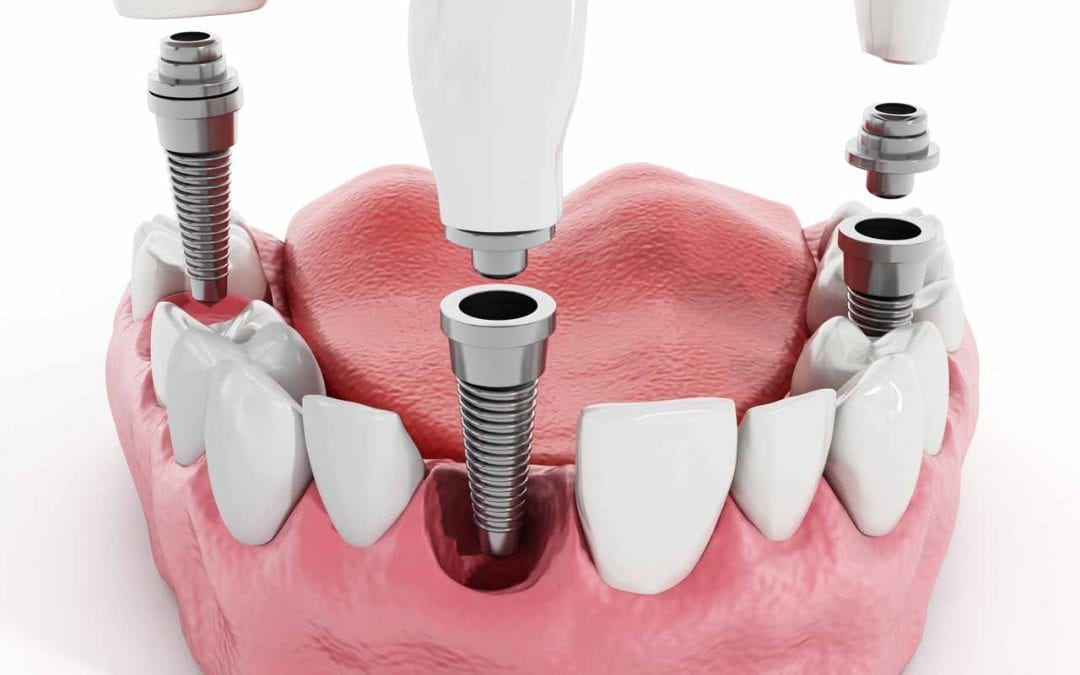

Pterygoid Dental Implants are a specific type of dental implants that are used for full-mouth rehabilitation in patients with insufficient bone volume in the upper jaw. They are named 'Pterygoid' because they are placed in the pterygoid plate, which is part of the sphenoid bone at the back of the upper jaw.

Pterygoid Implants are longer than conventional implants, typically measuring between 15 to 20 millimeters. Their increased length provides added stability and allows them to harness support from the dense pterygomaxillary region, eliminating the need for sinus lift procedures or bone grafts, which are often required with other types of implants. Thus, they offer a viable and effective solution for patients who have been told they are not suitable candidates for traditional implants due to lack of bone mass.

As Pterygoid Dental Implants are anchored in the pterygoid plates, they provide a firm and stable foundation for prosthetic teeth, ensuring optimal functionality and appearance.